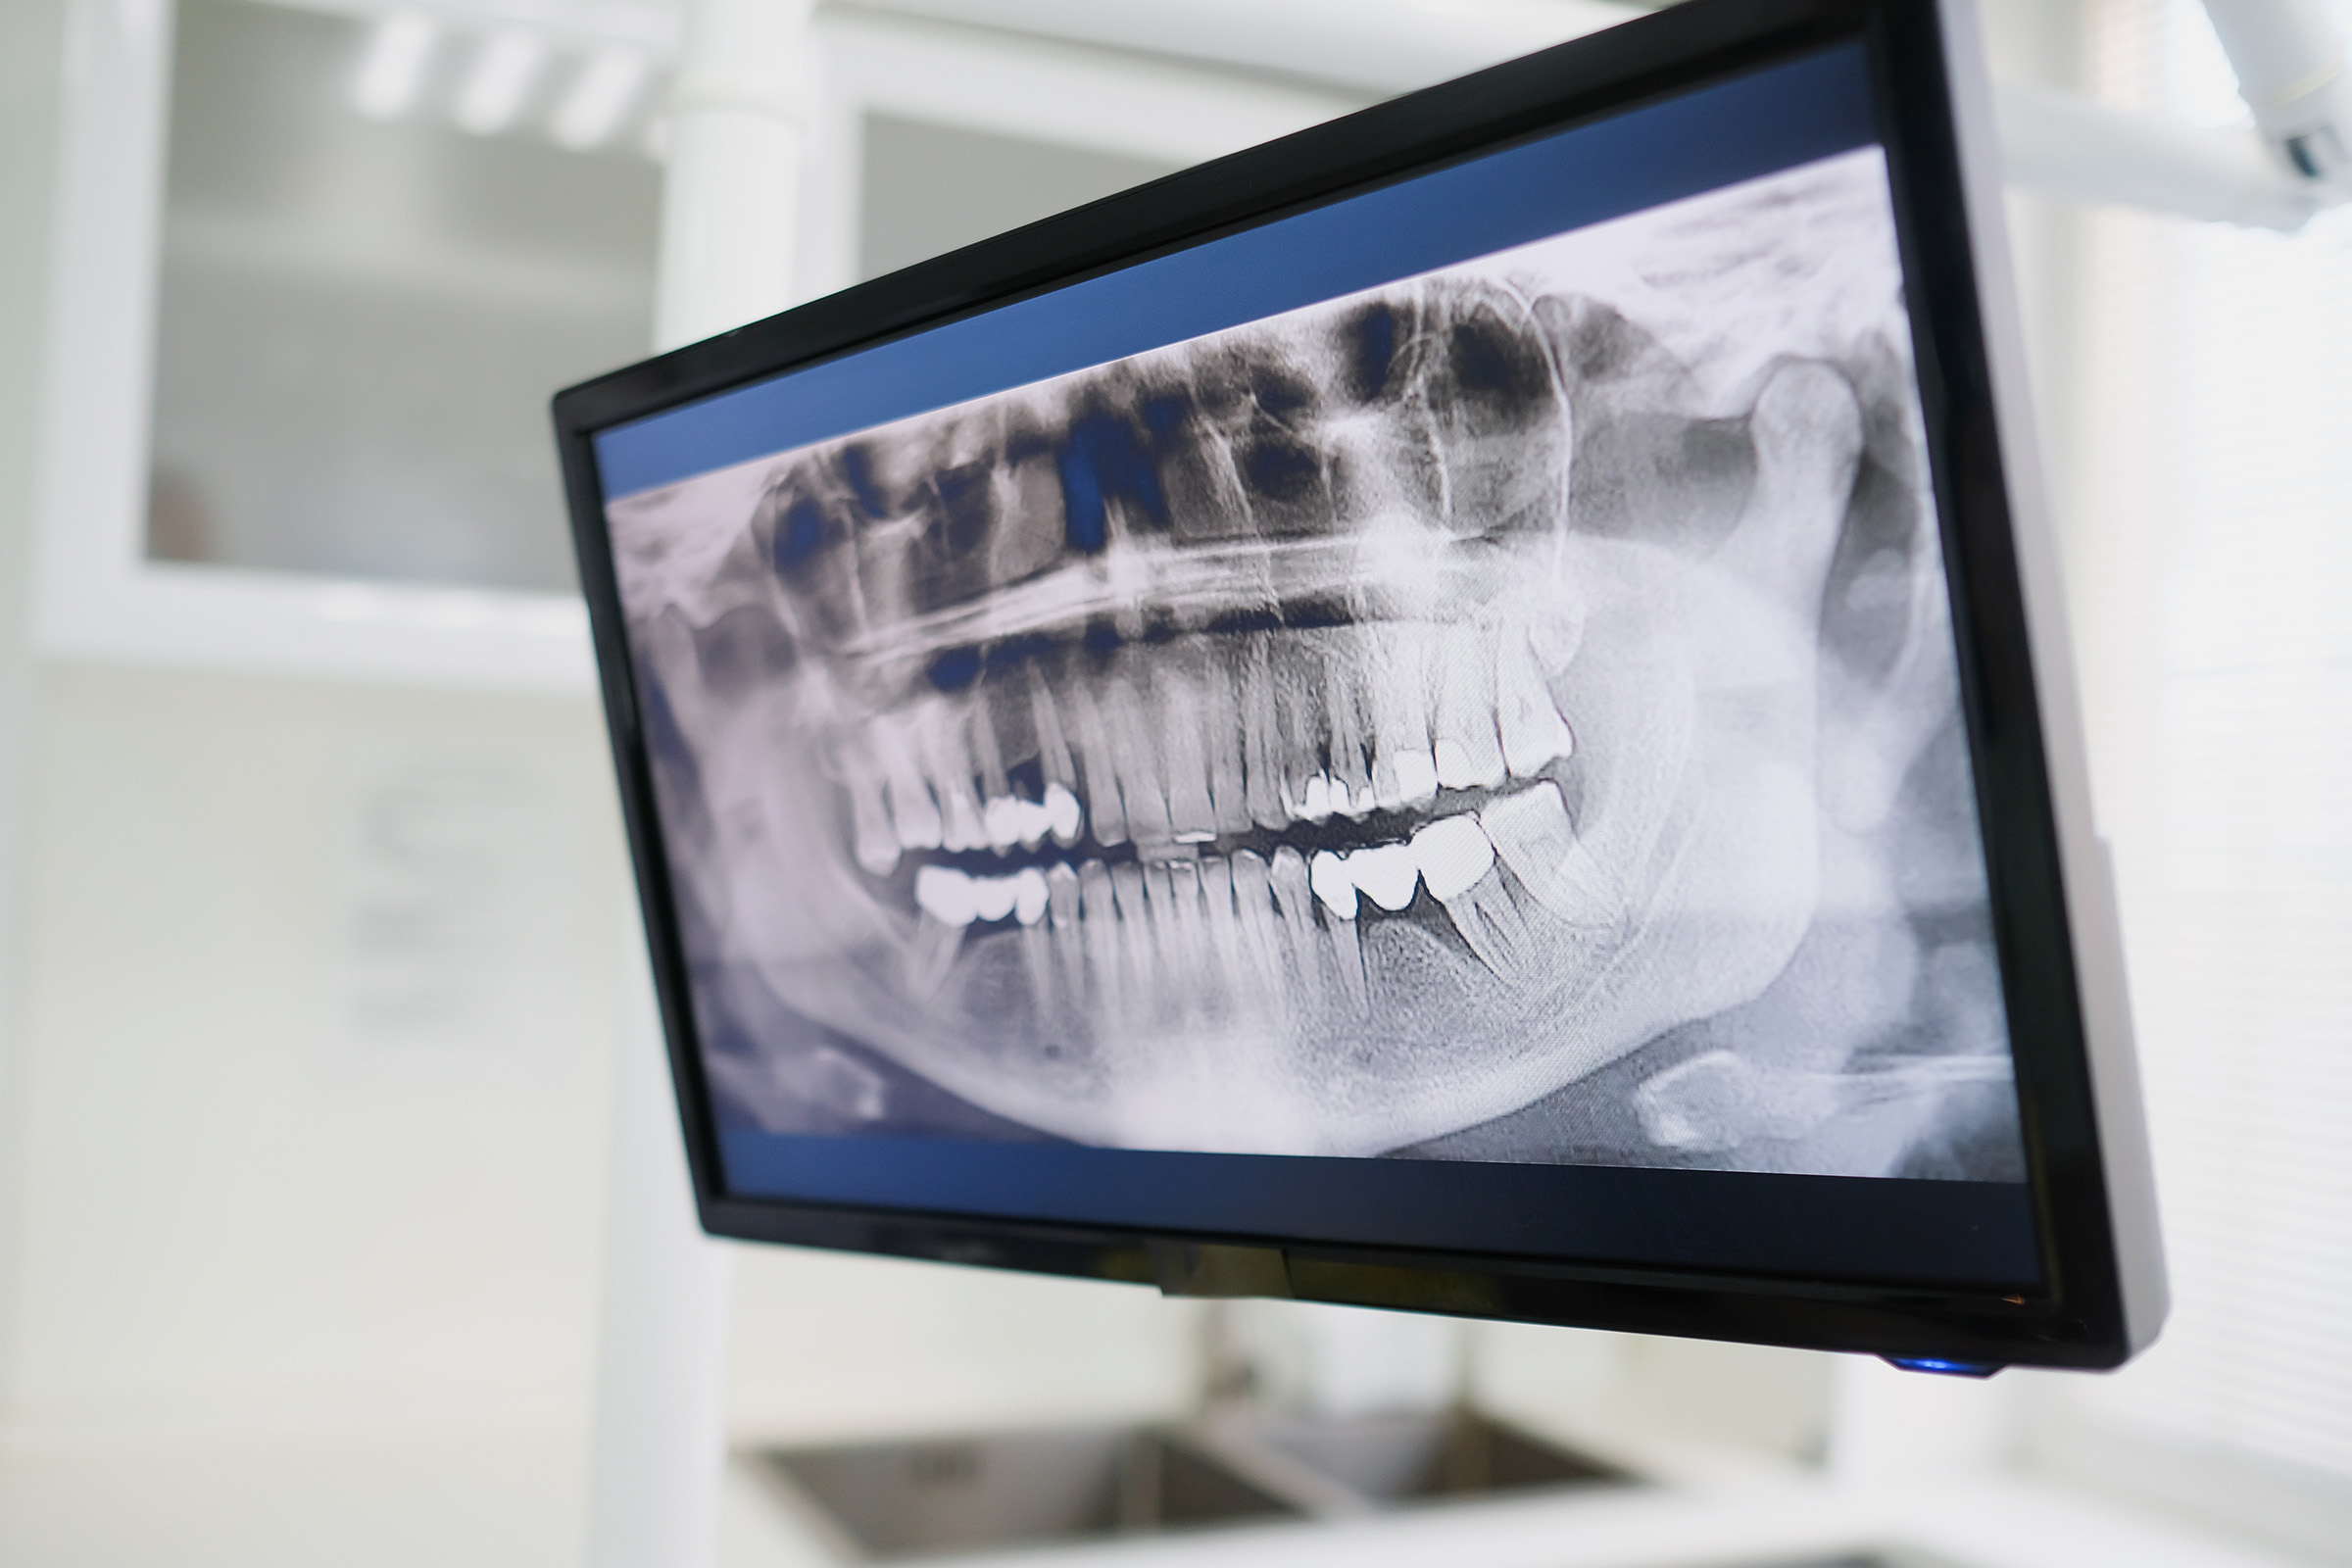

La radiografia dell’articolazione temporo-mandibolare è un esame che permette di visualizzare il tessuto osseo e lo scheletro in modo diverso rispetto ai tessuti molli: infatti il tessuto osseo è più compatto e in radiografia appare più chiaro rispetto agli altri tessuti.

L’esame prevede due proiezioni: una con la bocca chiusa e una con la bocca aperta per valutare le differenti posizioni durante masticazione.